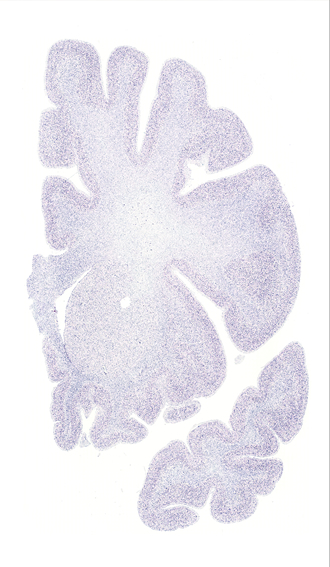

Hi-Resolution Sections · Cells (Nissl Staining) · Virtual Microscopy

Frontal sections (Nissl) from the Atlas Brain:

Slice ID:

r2-0352

Plate NR:

12-13

Position:

-13,7 mm